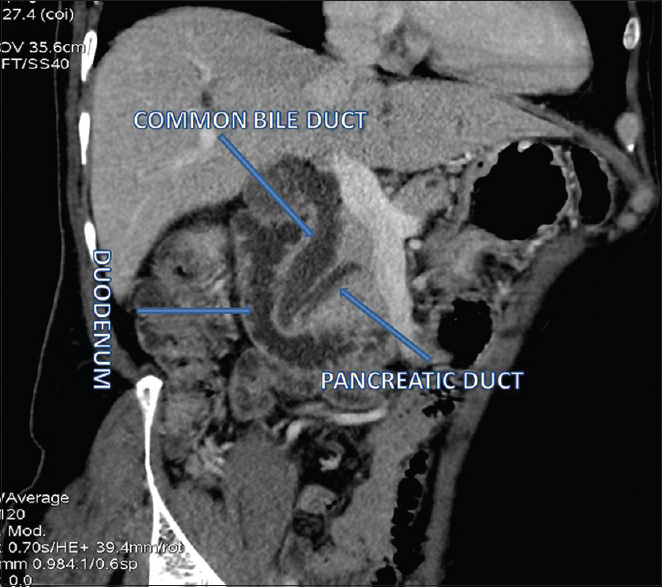

sphincter of Oddi dysfunction

can develop after any inflammatory process - surgery, pancreatitis

dyskinesia and stenosis of sphincter

opioids (morphine) cause contraction of sphincter –> precipitate sxs

manometry is the gold std dx

tx - sphincterotomy